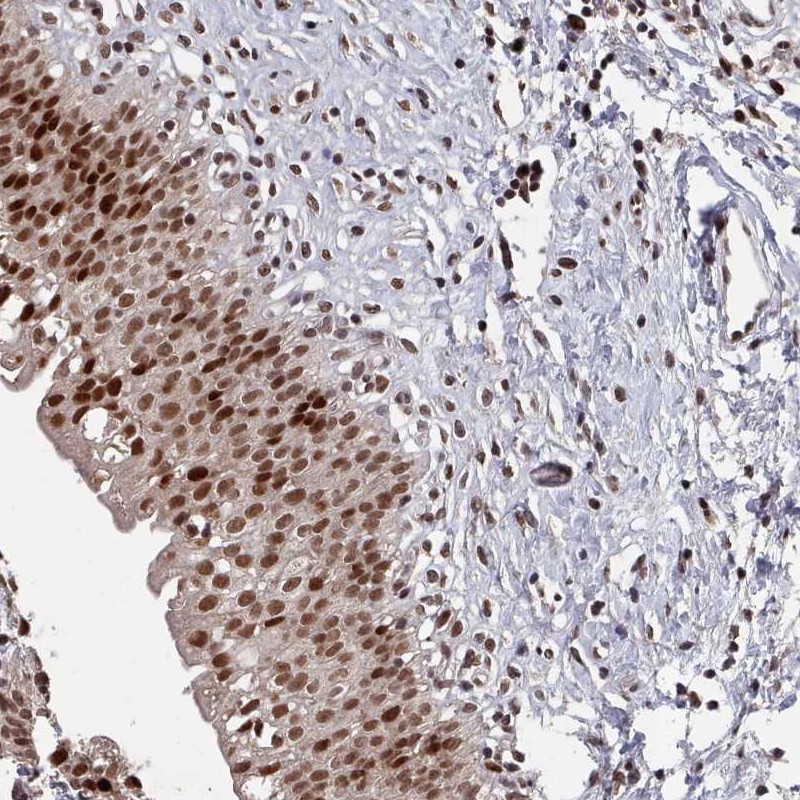

Immunohistochemical staining of human urinary bladder shows strong nuclear positivity in urothelial cells.